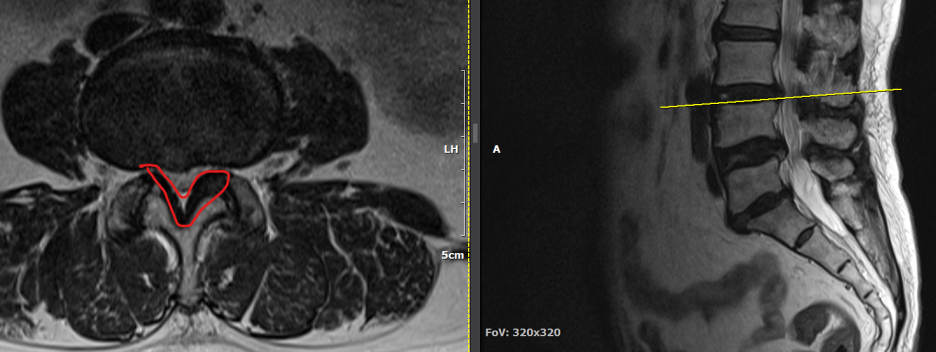

척추관 협착증은 척추관이 좁아지거나 협착되어 척수나 신경근을 압박하는 상태를 말합니다. 이런 경우, 양방향 척추 내시경이 매우 유용한 치료 수단이 될 수 있습니다.

- 계획: 양방향 척추 내시경은 미세한 카메라와 도구를 사용하여 척수와 주변 신경 구조를 정밀하게 시각화할 수 있습니다. 이를 통해 정확한 진단을 내릴 수 있으며, 각 환자에게 맞는 개별적인 수술 계획을 수립할 수 있습니다.